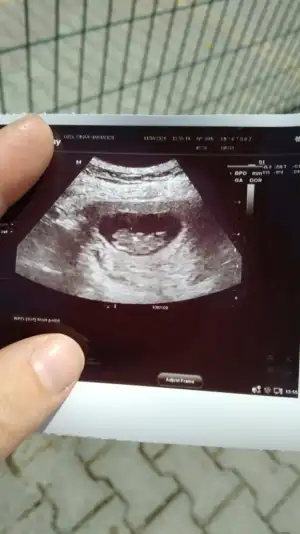

Erkek görünüyor

Yaaaa doktor kız demişti %85Erkek görünüyor![]()

Pardon cnm duzeltiyorum sanada erkek demis baska sayfada ❤Yaaaa doktor kız demişti %85bir oğlum var sağlıkla kız olsun çok isterim nub u kesin erkekmi

Önceki usg kaç haftalık bu kaç haftalik önceki daha net ise erkektir 11 12 13 haftalar olmalıTsk ederm canm önceki fotolarda erkek demistin ama sorun yok 1 ay sonra öğrenince oylayacagim anketini![]()

Bana göre hiçbiri net değilÖnceki usg kaç haftalık bu kaç haftalik önceki daha net ise erkektir 11 12 13 haftalar olmalı